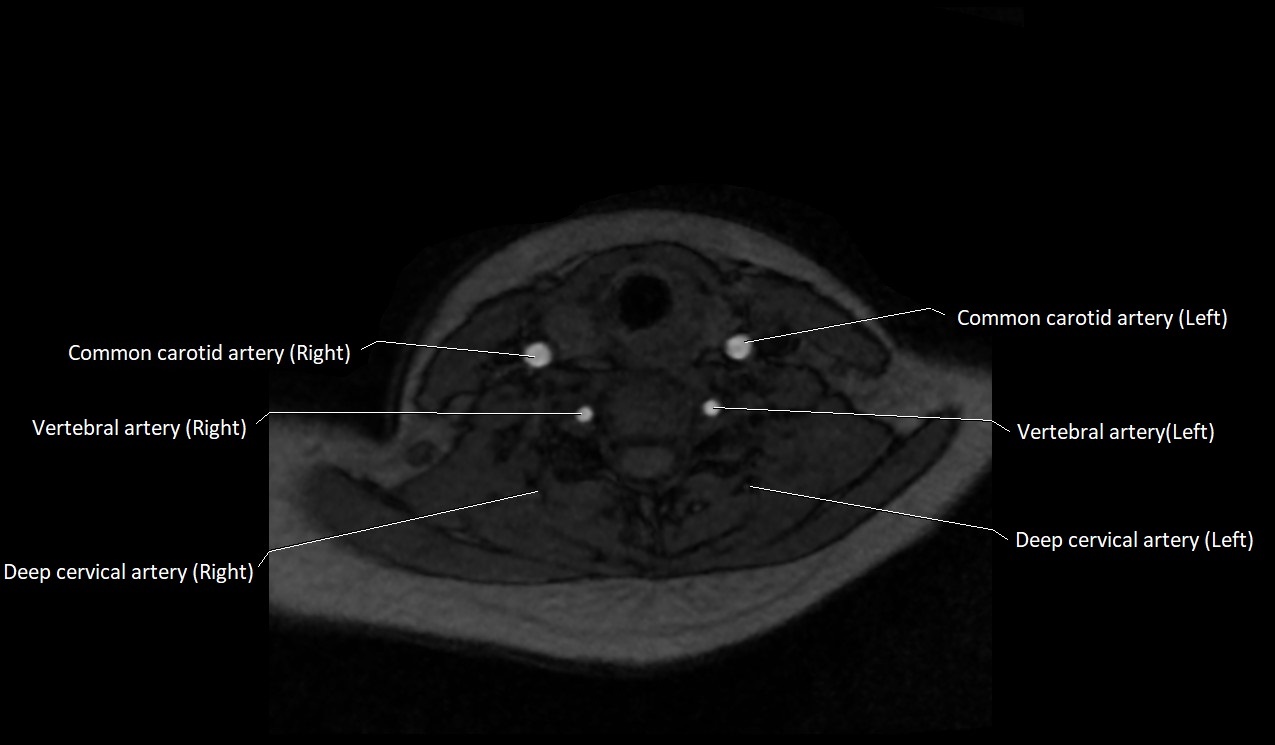

CT image

image